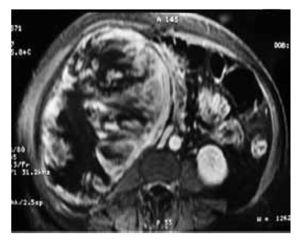

Paciente femenina de 71 años de edad, padre diabético, madre hipertensa. Acudió por masa dolorosa en flanco derecho, de 2 meses de evolución, asociada a pérdida de peso de 7 kg y escalofrío eventual. A la exploración física con presión arterial de 120/80 mmHg, tórax normal, abdomen blando, depresible, masa dura, dolorosa, que involucra todo el hemiabdomen derecho. Exámenes de laboratorio con Hb: 10.7, creatinina: 1.22, examen general de orina: 3-4 eritrocitos por campo, pruebas de funcionamiento hepático normales, radiografía de tórax normal, tomografía computadorizada y angiorresonancia: masa sólida heterogénea, con áreas de necrosis y con escasa captación de contraste, sin afección de grandes vasos (Imágenes 3 y 4). Se efectuó nefrectomía radical, tumor con dimensiones de 27 x 15 x 18 cm dependiente de polo inferior (Imagen 5).

Imagen 3. Tomografía computadorizada a los dos meses de evolución, en la que se identifica una masa sólida heterogénea.

Imagen 4. Angiorresonancia: masa sólida heterogénea, con áreas de necrosis y con escasa captación de contraste, sin afección de grandes vasos con áreas de necrosis y con escasa captación de contraste, sin afección de grandes vasos.